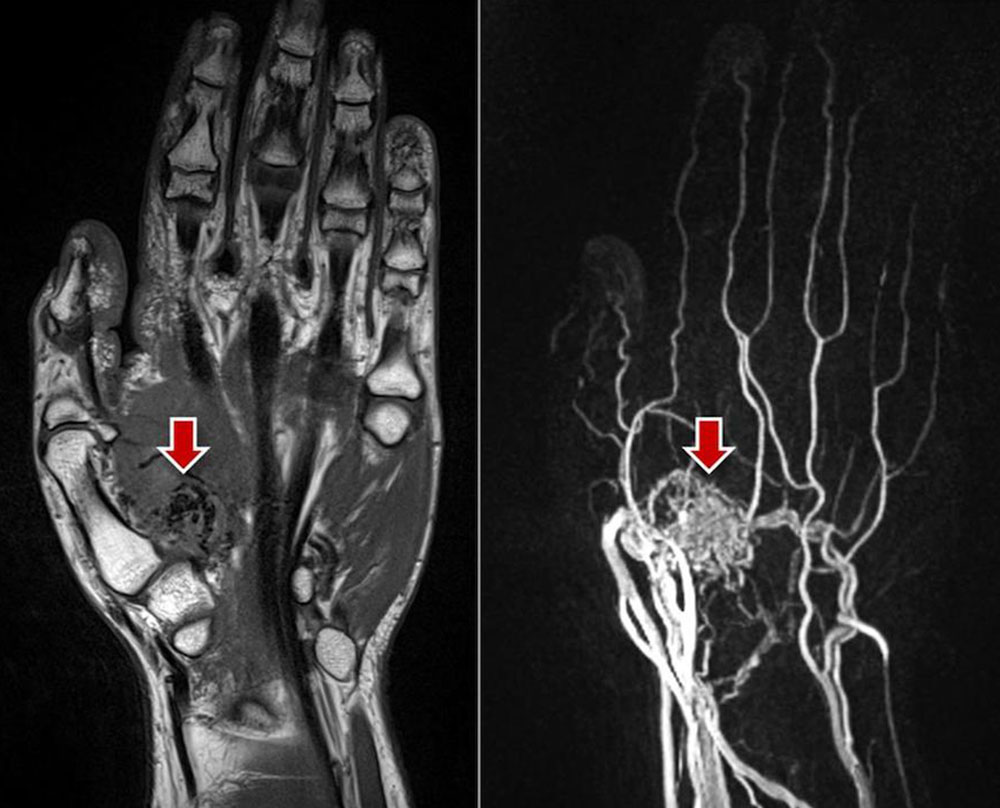

Arteriovenous malformation: The morphologic correlate of the arteriovenous malformation, the so-called nidus (network of direct arteriovenous shunts), is often very hard to detect on native MRI sequences as a solid component is missing in AVMs. Occasionally, the AVM is surrounded by edema or connective and fatty tissue. Typically, spin-echo sequences (T1 or T2) show flow voids within the vessel channels because of high flow velocity. Diagnosis can ultimately be made with the help of dynamic MR angiography with high spatial and temporal resolution. Here, the nidus and the dilated, draining veins are contrasted almost immediately via the corkscrew-like dilated arterial feeders. In lesions located in the extremities, the inflowing and outflowing vessels are usually significantly enlarged compared to the unaffected side. In some cases the vessels are degenerated and show aneurysmal dilatations (so-called flow-related aneurysms). On account of the shunt with low flow resistance, normal vessel sections distal to the shunt may no longer be visible on MRA because of a steal phenomenon. The tissue surrounding the nidus typically does not show contrast enhancement and is hardly recognizable as the actual lesion since the lesion lacks a solid component. However, after invasive procedures or during an inflammatory or proliferative phase, surrounding edema with contrast enhancement is occasionally visible.